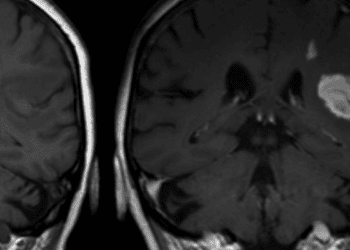

1. Parenchymal hypoattenuation of greater than 33% of the middle cerebral artery (MCA) territory on computed tomographic (CT) imaging within 6 hours of onset of an acute stroke was predictive of poor neurologic outcomes with intravenous thrombolytic therapy (tPA) and an increased risk of hemorrhagic conversion.

2. Like those with a large area of focal hypoattenuation, patients without parenchymal abnormalities on CTshowed a significantly increased risk of cerebral hemorrhage and no significant change in neurologic outcomes at 90-days post-tPA; however, those with small (< 33% of MCAterritory) regions of hypoattenuation showed a significant improvement in long-term function.

Study Rundown: Acute ischemic stroke occurs when blood supply to a region of the brain is disrupted, leading to characteristic symptomatology related to the location of the lesion. After clinical examination, the mainstay of stroke diagnostics depends upon neuroimaging to aid in lesion localization and characterization of its type, size, and the extent of irreversible ischemia to guide therapeutic intervention. While recent trials have established mechanical thrombectomy as the optimal therapeutic strategy in large-vessel occlusions, the initial management of ischemic strokes presenting within 3-6 hours of onset was previously established by the ECASS and NINDS trials, which revealed that early tPA administration may achieve chemical recanalization and improve neurologic recovery. Both modern directed intra-arterial therapies and standard intravenous tPA administration are predicated on the concept that the affected tissue has not progressed to complete infarction, or that there is a region of hypoperfused or “penumbral” tissue within the affected vascular territory that may be rescued by the restoration of blood flow. The referenced study sought to determine if a large area of hypoattenuation on initial CT, indicative of terminal ischemic edema, may portend poorer outcomes with standard tPA treatment. Patients presenting with acute ischemic stroke within 6 hours of symptom onset underwent baseline head CT and were randomized to receive either tPA or placebo. Patients were then prospectively subcategorized into one of three groups according to the extent of visible MCA territorial hypoattenuation: no visible defects, 33% or less, or more than 33% of the region affected, and neurologic outcomes were recorded at 90 days post-treatment. The authors found that those with greater than 33% of the MCA territory visibly hypoattenuated and those with no visible hypoattenuation on initial CT imaging did not have a statistically significant improvement in long-term neurologic recovery, but did suffer a significantly increased risk of fatal cerebral hemorrhage secondary to tPA therapy. Those with hypoattenuation visible in less than 33% of the MCA territory were not at significantly increased risk of hemorrhagic conversion and demonstrated an improvement in long-term neurologic recovery, as observed in the previously referenced trials. This analysis was instrumental in demonstrating that the extent of completed ischemia visible on CT could predict outcomes after stroke therapy.

In-Depth [randomized controlled trial]: A total of 620 patients presenting with acute, ischemic hemispheric stroke within 6 hours of symptom onset were randomized to either receive intravenous tPA or placebo in a double-blinded fashion across multiple European medical centers. All patients underwent baseline head CT, and were prospectively categorized into one of three groups according to the extent of hypoattenuation visible within the affected MCA territory: no hypoattenuation visible, less than 33% (small territory), or greater than 33% (large territory.) Of those enrolled, 336 patients had no visible parenchymal hypoattenuation, while 215 displayed a small region, and only 52 displayed a large region of hypoattenuation, and no significant differences in baseline characteristics were noted between the subcategories except for their presenting clinical stroke scores (progressively worsened for those with larger areas of infarction; p < 0.0001.) The degree of presenting hypoattenuation was significantly associated with an increased baseline risk of poor neurologic outcomes as assessed within the placebo-treated groups (p < 0.0001). Among patients treated with intravenous tPA, no statistically significant effect on long-term neurologic recovery was noted for patients with either no initial parenchymal hypoattenuation or those with a large area of parenchymal hypoattenuation. However, 14 of 198 patients (7%) in these two groups died secondary to cerebral hemorrhage, while only 2 of 190 patients (1%) in the corresponding placebo-treated groups suffered the same complication. Patients who presented with a small area of hypoattenuation displayed an OR for good neurologic recovery of 3.43 following tPA treatment, while those with a large or no area of hypoattenuation did not show a significant difference in their odds of recovery (OR 0.41, 95%CI 0.06-2.70; OR 1.27, 95%CI 0.82-1.95, respectively.) This study established the lack of benefit and subsequent risks of utilizing intravenous thrombolytic therapy in patients with greater than one-third of the MCA territory visibly infarcted.